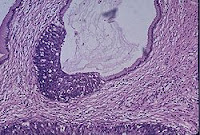

Neoplastik değişiklikler skuamokolumnar bileşkeden (junction) başlar. Serviks kanseri gelişmesinde serviks epitelinde birbiri ardısıra gelen değişiklikler olur, bu da serviks kanserinin erken tanısında önem taşır.

Bu değişiklikler sırasıyla:

1. Normal endoservikal kolumnar epitel

2. Skuamöz metaplazi

3. Hafif-orta-ağır displazi

4. Karsinoma in situ

5. Mikroinvazif karsinom

6. Belirgin invazif karsinom, şeklindedir.

Premalign lezyonların evrelendirilmesi

Preinvaziv servikal hastalık kavramı, 1947 senesinde invaziv kanser görünümüne sahip ancak epitelle sınırlanan epitelial değişiklikler tanımlandığında ortaya atılmıştır. Displazi ve CIS’ın (Karsinoma in situ) sürekli bir olayın farklı basamaklarını teşkil ettiğini düşünen Richart, 1967 yılında servikal intraepitelial neoplazi (CIN I, II, III) terimini tanımlamıştır. Sonraki çalışmalar bu lezyonların tedavi edilmemeleri halinde servikal kansere yol açabileceğini gösterdi. Şimdi ise tedavi edilmediği zaman erken CIN lezyonlarının çoğunun eş zamanlı olarak gerilediği bilinmektedir. Günümüzde anormal lezyonların gelişiminde premalign displastik değişikliklerin değerlendirilmesi için CIN sistemi kullanılmaktadır.

Servikal intraephitelial neoplazi (CIN):

* CIN I Hafif displazi (atipik hücreler epitelin alt 1/3’ünde sınırlı)

* CIN II Orta displazi (atipik hücreler epitelin alttan 2/3’lük kısmında ise)

* CIN III Ağır displazi (epitelin tamamına yakını tutulmuş ise)

* CIS Karsinoma in situ (epitelin tamamı tutulmuşsa)

Not I: CIN I düşük evreli skuamöz intraepitelyal lezyon; CIN II/III yüksek evreli skuamöz intraepitelyal lezyon olarak da isimlendirilir.

Not II: Bütün lezyonlarda bazal membran sağlamdır.

İnvaziv servikal kanserler genellikle uzun bir preinvaziv hastalık evresini izlerler. Mikroskopik olarak, invaziv karsinomlara ilerlemeden önce hücresel atipiden, değişen derecelerde servikal intraepitelyal neoplazilere (CIN) ilerleyen prekürsor lezyonlar spektrumu ile karakterizedir. CIN I lezyonlarının büyük çoğunluğunun geçici olduğu; kısa dönemlerde normale gerilediği veya yüksek derecelere ilerlemediği iyi bilinmektedir. Diğer taraftan, yüksek dereceli (CIN II, III)’ler, her ne kadar bu tür lezyonların da bir kısmı gerilese de, yüksek oranda invaziv kansere ilerleme olasılığı taşır. Servikal öncü lezyonların invaziv kansere ilerlemesinin ortalama 10 ila 20 yıl kadar uzun bir zaman aldığı bilinmektedir.